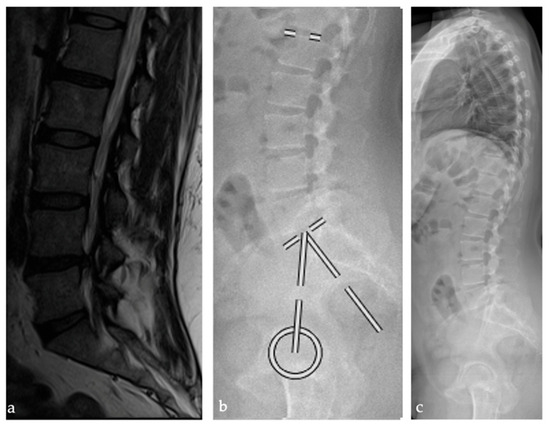

2.2. Radiographic Analysis